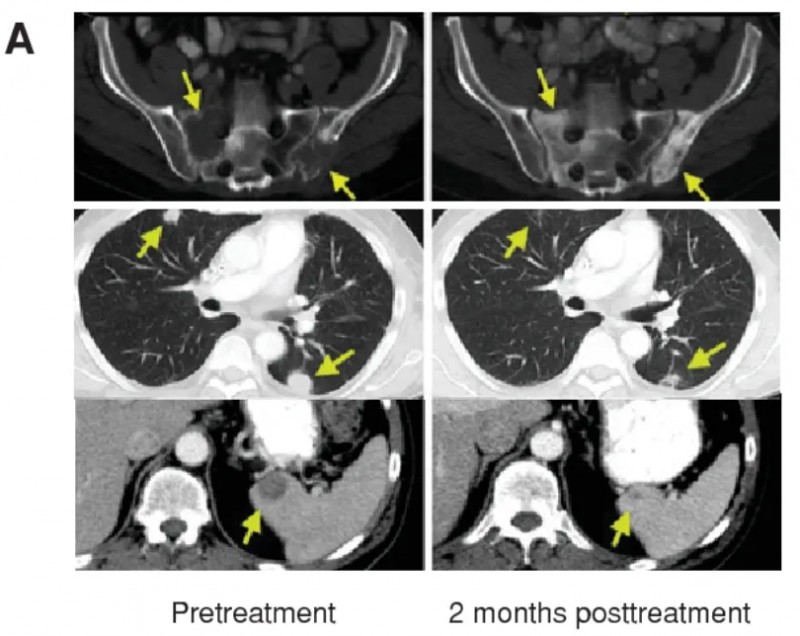

晚期全身转移黑色素瘤(一)

已经出现肺、脾脏,骨转移的晚期黑色素瘤患者,接受TIL疗法后,所有病灶在2个月后均显示消退。